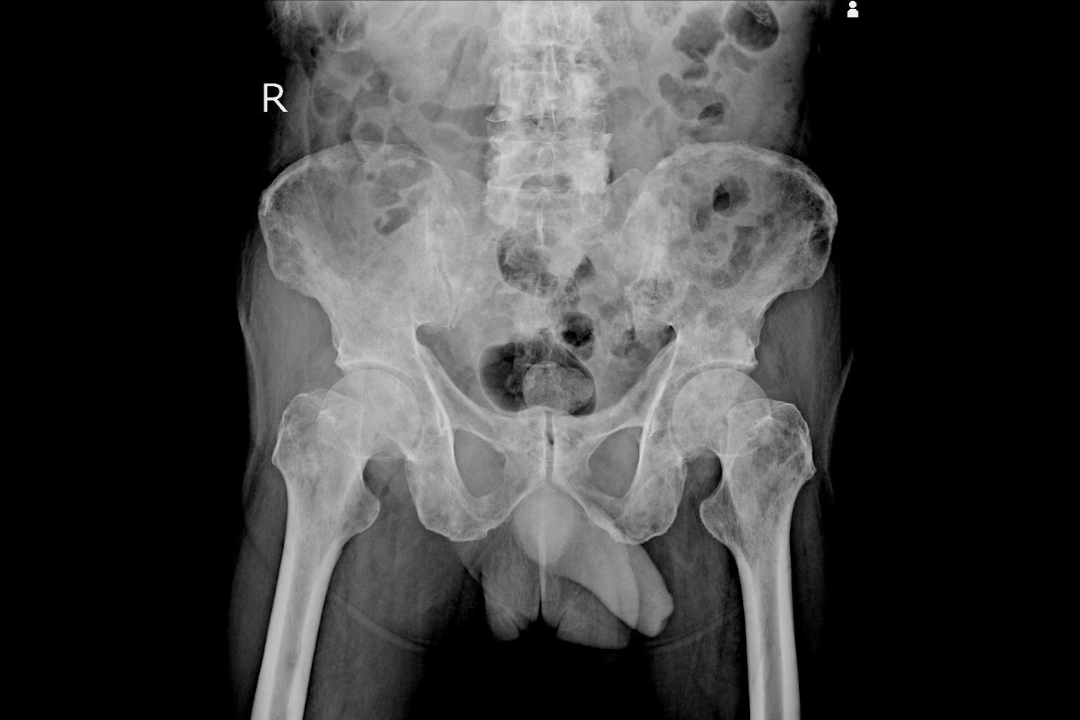

bone metastasis Singapore.

• Imaging test – X-rays, CT scans, MRI or bone scans may be used to locate bone metastases, assess the extent of spread and rule out fractures or nerve compression.